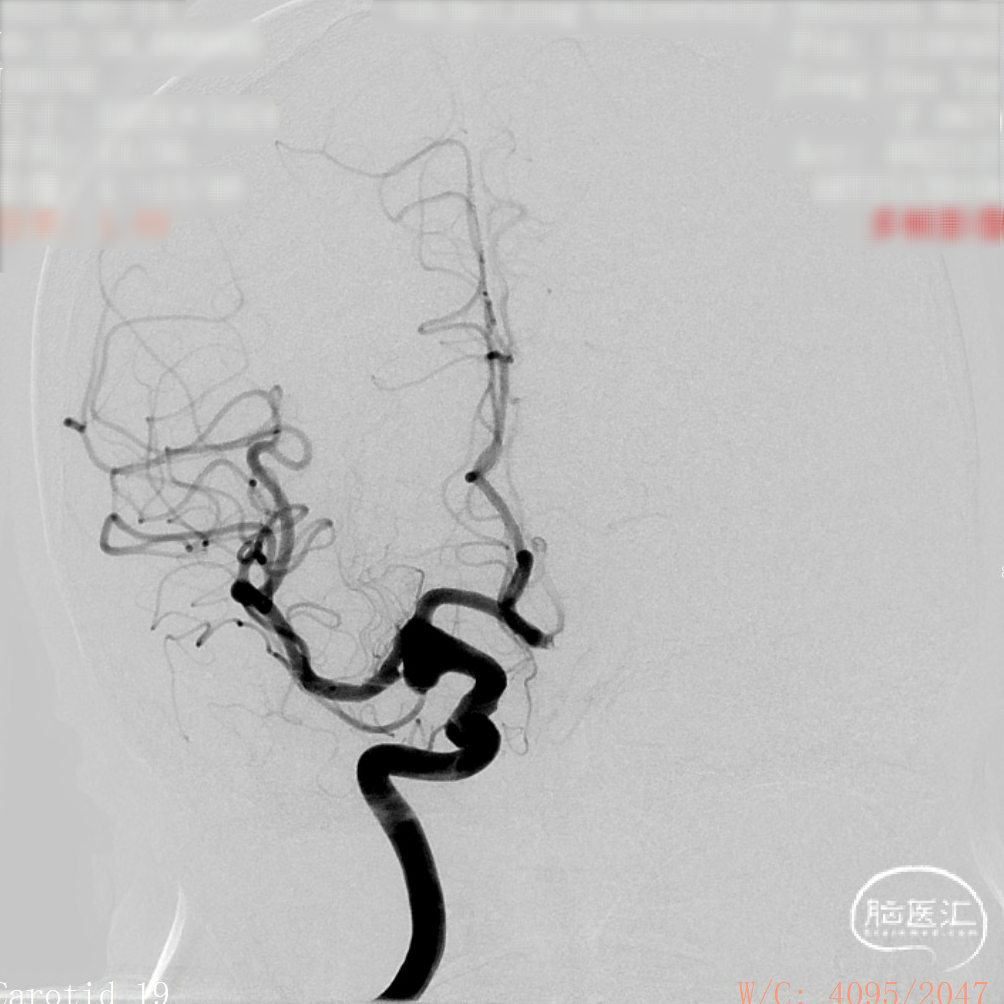

DSA造影:

工作角度:

正侧位造影:支架放置后可见动脉瘤内造影剂明显滞留。

大动脉瘤的微创介入栓塞治疗存在需要支架辅助,瘤颈处理困难、复发率高、费用高等难点;血流导向密网支架置入是较优选择,操作相对简单,不用填塞弹簧圈,完整覆盖瘤颈,远期明显降低再复发概率。本病例为右侧颈内动脉C7段累及脉络膜前动脉的大动脉瘤,该部位解剖结构复杂,周围血管分支多,在操作过程中要避免损伤正常血管,否则会引发严重脑缺血事件;其次,动脉瘤与脉络膜前动脉关系密切,既要处理好动脉瘤,又要保证脉络膜前动脉的血供不受影响,这对手术操作精度要求较高;再者,瘤颈的处理较为棘手,瘤颈较宽,传统弹簧圈栓塞难以达到理想效果,且容易复发。血流导向密网支架置入可解决这些问题,术前需借助3D-DSA,全面评估动脉瘤大小、形态、瘤颈宽度、与周围血管关系,制定精准手术方案。操作时,微导管的到位是关键一步,要在路径图引导下,小心、轻柔操作,避免刺激血管引发痉挛或动脉瘤破裂。释放支架过程中,要注意关注支架位置和贴壁情况。释放后要通过多角度造影,确认支架完全覆盖瘤颈,且支架内血流通畅,分支血管未受影响。同时,术后要密切观察患者神经功能变化,预防血栓形成、血管痉挛等并发症,及时给予抗血小板、解痉等药物治疗。